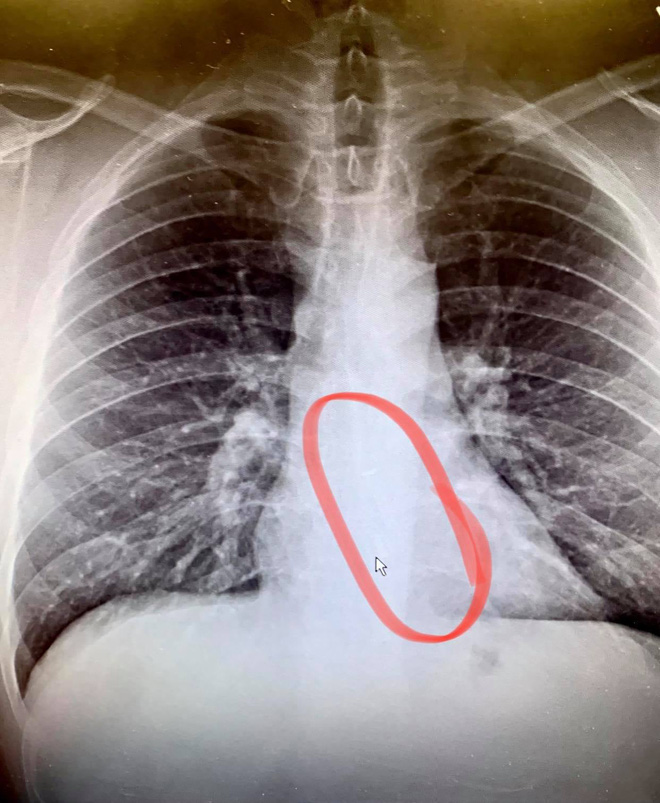

07/02/2021 22:00Đeo tai nghe lúc ngủ, anh thanh niên vô tình nuốt luôn 1 bên AirPods khiến nó kẹt cứng ở thực quản

Sự cố hi hữu này xảy ra với Bradford Gauthier, sống tại Worcester, Massachusetts, Hoa Kỳ, khi anh nuốt phải 1 bên tai AirPods trong lúc ngủ và phải nhập viện cấp cứu để lấy nó ra. Gauthier cho biết khi tỉnh dậy, anh vẫn cảm thấy bình thường, nhưng lúc uống nước thì nước không trôi xuống và buộc phải nôn ngược trở lại. Lúc này, anh mới bắt đầu phát hiện ra có gì đó nặng trĩu, gây ra nhiều áp lực ở vùng ngực của mình, nhưng cho rằng đó chỉ là cổ họng anh bị khô sau khi dọn tuyết đêm qua.

Mặc dù có đôi chút nghi ngờ về cơn tức ngực kì lạ và sự biến mất bí ẩn của 1 chiếc AirPods, nhưng Gauthier đã nhanh chóng tự mình bác bỏ ý kiến này. Tuy nhiên, hình ảnh chụp X-quang tại bệnh viện đã cho thấy điều ngược lại, với 1 bên tai nghe mắc kẹt bên trong thực quản của anh. Sau khi tiến hành cấp cứu thành công, Gauthier cho biết: “Tôi không thể ngờ sử dụng AirPods trong lúc ngủ lại có thể gây ra nguy hiểm chết người như vậy. Quả thật lần này tôi đã rất may mắn”. Anh cũng không quên nhắc nhở mọi người về rủi ro tương tự khi nghe nhạc bằng tai nghe không dây lúc đi ngủ.